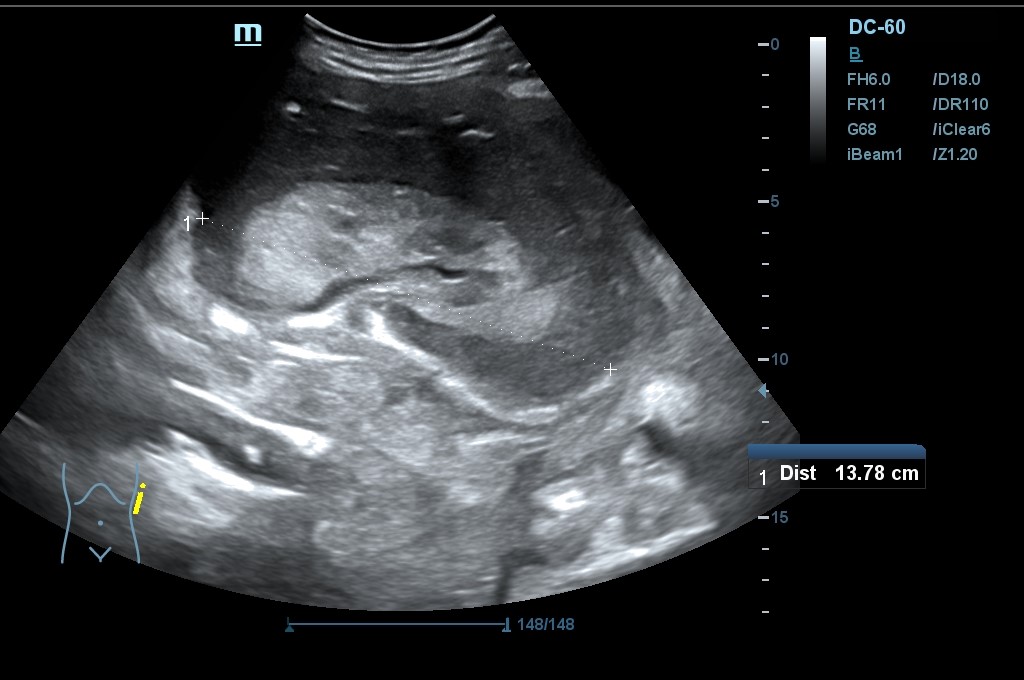

Hallazgo de lo que impresiona de nefromegalia izquierda de aproximadamente 14 cm con hidronefrosis bilateral grado 2.

Tras la segunda ecografía se deriva a la paciente a la Unidad de Diagnóstico Rápido de Medicina Interna donde ingresa para completar estudio. Tras ecografía en la que informan de extenso tejido hipoecoico periaórtico y perirrenal izq. (nefromegalia izq.) con extensión nodular al mesenterio, se establece la sospecha de síndrome linfoproliferativo, así como en un TC posterior y que se confirma como Linfoma No Hodgkin mediante biopsia.